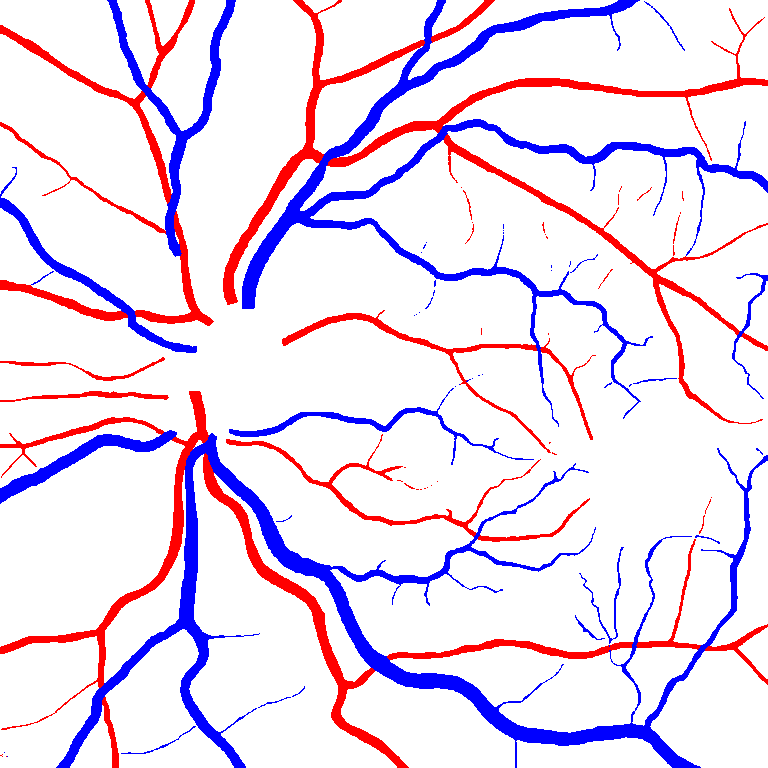

As reported in Table IV, we compared the SegRAVIR model against competing deep learning-based segmentation approaches on the RAVIR dataset. Evidently, SegRAVIR outperforms these methods as judged by all metrics for artery and vein classes with a healthy margin. In terms of Dice score, SegRAVIR outperforms CE-NET, IterNet and AG-Net by , and for artery segmentation and by , and for vein segmentation, respectively. Fig. 4 presents a qualitative comparison of the semantic segmentation outputs of SegRAVIR, CE-Net, and U-Net. Specifically, SegRAVIR yields more accurate vessel topology (i.e., thickness and orientation) segmentation with higher pixel-wise classification accuracy.

Table V presents quantitative performance benchmarks of SegRAVIR and other competing approaches for retinal artery and vein classification on the RITE dataset [11]. SegRAVIR outperforms previous state-of-the-art approaches in terms of accuracy, sensitivity, and specificity. Fig. 5 provides a qualitative comparison between segmentation outputs of SegRAVIR and the method of Hemelings et al. [40] on the RITE test set.